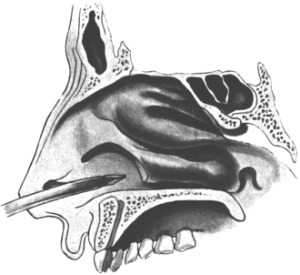

| 345. | Catheterizing the Sphenoidal Sinus | 654 |

| 346. | Killian’s Long Nasal Speculum | 655 |

| 347. | Radiograph showing a Probe in the Sphenoidal Sinus | 657 |